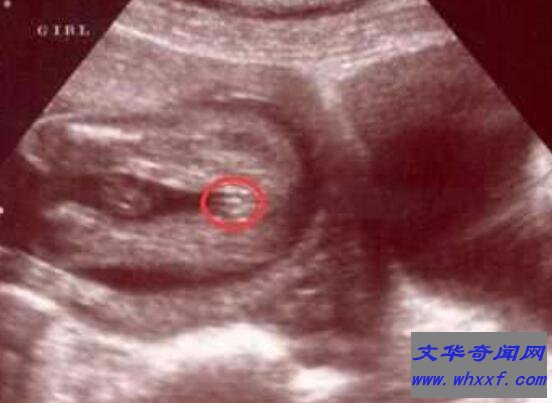

1、B超

在医院做B超是最容易看出是男孩还是女孩,它主要是通过超声波扫描,在图像上显示男孩和女孩决然不同生殖器官,不过也不排除看不清楚情况。一般来说,超声波在检测胎儿性别时候,男婴正确率要高于女婴的,当然也有一定检测误差。